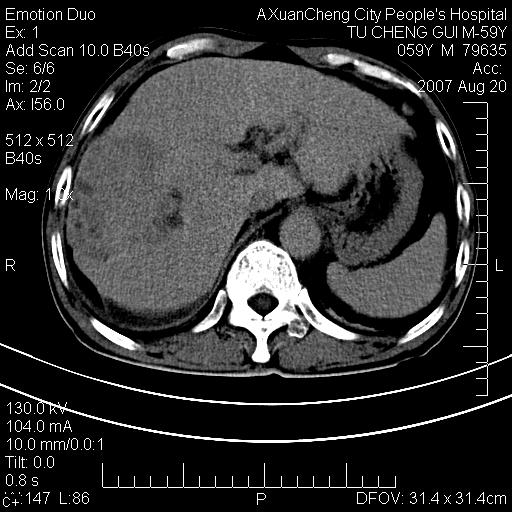

标题: CT9451:M59Y,肝脏占位

肝区涨痛一周,肝功能转氨酶均轻度增高

增强

典型的肝癌(巨块型)、腹水,有供血动脉。

巨块性肝癌!(平扫不均匀低密度,增强方式典型的快进快出)

典型的快进快出,动脉期可见肿瘤组织的供血动脉,肝下间隙可见条带状水样低密度区,符合原发性肝癌的ct表现。可以查一个afp >300有意义

患者有肝硬化,平扫病灶呈不均性低密度,增强呈快尽快出表现,内见更低密度灶,静脉期延迟期呈低密度符合肝癌表现,内低密度为坏死改变并少量胸腹水。

动脉期肝右动脉粗细不均,走行有点迂曲,门脉期门脉右支有点受侵,并且中心有坏死,呈快进快出,符合肝癌

典型肝癌ct表现(肝右叶肿块密度不均,增强典型快进快出,内部有液化坏死,可能有脂肪变性)。

肝右叶巨块型肝癌伴少量腹水.双侧少量胸腔积液.